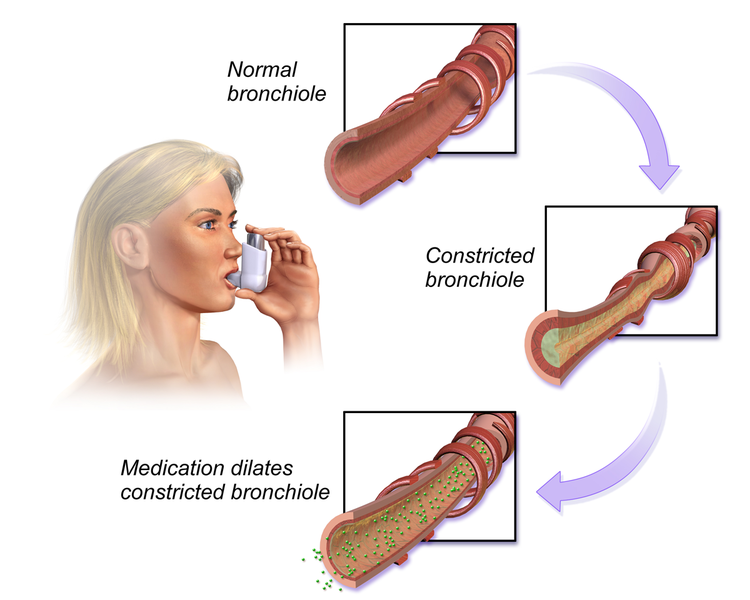

- Bronchodilators – are generally offered and provided to patients with substantial airflow obstruction to reduce airway inflammation and narrowing.

Bronchodilators